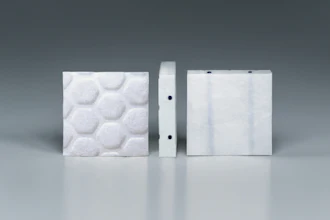

The Injectsense IOP-Connect Sensor Platform sensors in a custom carrier.Injectsense

The Injectsense IOP-Connect Sensor Platform sensors in a custom carrier.Injectsense